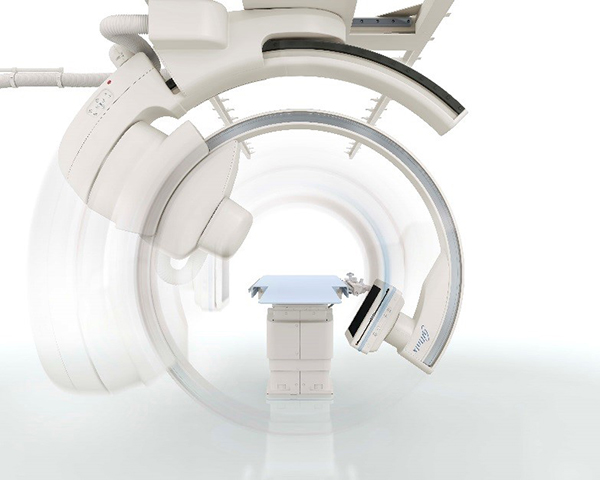

Ця ангіографічна система з кріпленням на стелі спеціально розроблена для використання в операційній кімнаті. С-арка інтегрується з операційним столом та встановлюється в операційній.

Система зі стельовим кріпленням розроблена з урахуванням використання ламінарного потоку.

Широкі інтервали між стельовими рейками дозволяють забезпечити гігієнічні умови експлуатації.

Система Alphenix Hybrid+ (в основі якої система Sky+) має унікальну конструкцію подвійної С-арки, завдяки цьому забезпечується:

Завдяки ізоцентричному обертанню система Alphenix Hybrid+ забезпечує неперевершений доступ та покриття навіть при найскладніших втручаннях. Подвійна конструкція С-арки з можливістю обертанням як справа, так і зліва від пацієнта з найбільшою швидкістю дозволяє скоротити час затримки дихання, зменшити кількість контрасту та отримати бездоганний 3D об'єм від голови до п’ят без необхідності переміщувати пацієнта: